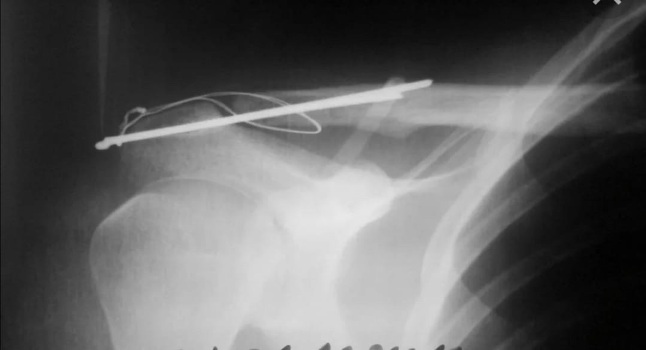

ОСТЕОСИНТЕЗ - это хирургический метод лечения переломов костей, при котором костные отломки фиксируются друг с другом при помощи специальных металлических конструкций (спицы, винты, штифты, гвозди).

Вид металлоконструкции и способ её установки подбираются врачом травматологом-ортопедом индивидуально.